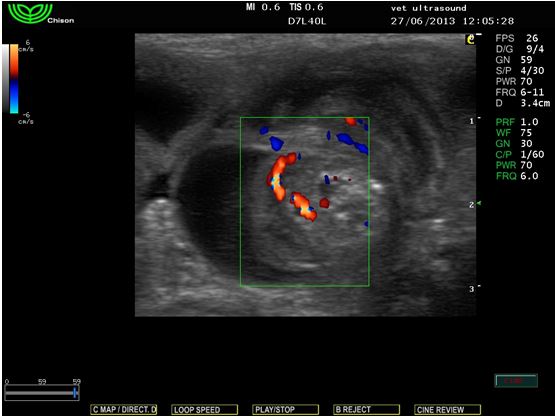

Έγινε υπέρηχος κοιλίας όπου εντοπίστηκε αφθονία ασκιτικού υγρού και εγκολεασμός μεγάλου τμήματος του πεπτικού σωλήνα. Το εγκολεασθέν μέρος του εντέρου ήταν το παχύ έντερο με την ειλεοτυφλική βαλβίδα. Στις εικόνες βλέπουμε το λεπτό έντερο να περιβάλλει το παχύ έντερο. Με τη βοήθεια του έγχρωμου Doppler βλέπουμε πως τα αγγεία του μεσεντερίου έχουν ροή, στοιχείο θετικό για την ζωτικότητα των εντερικών ελίκων.